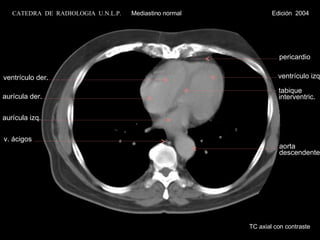

TC axial con contraste ventrículo der. aurícula izq. v. ácigos aurícula der. aorta descendente CATEDRA  DE  RADIOLOGIA  U.N.L.P.   Mediastino normal  Edición  2004 ventrículo izq. tabique interventric. pericardio

TC axial concontraste ventrículo der. aurícula izq. v. ácigos aurícula der. aorta descendente CATEDRA DE RADIOLOGIA U.N.L.P. Mediastino normal Edición 2004 ventrículo izq. tabique interventric. pericardio